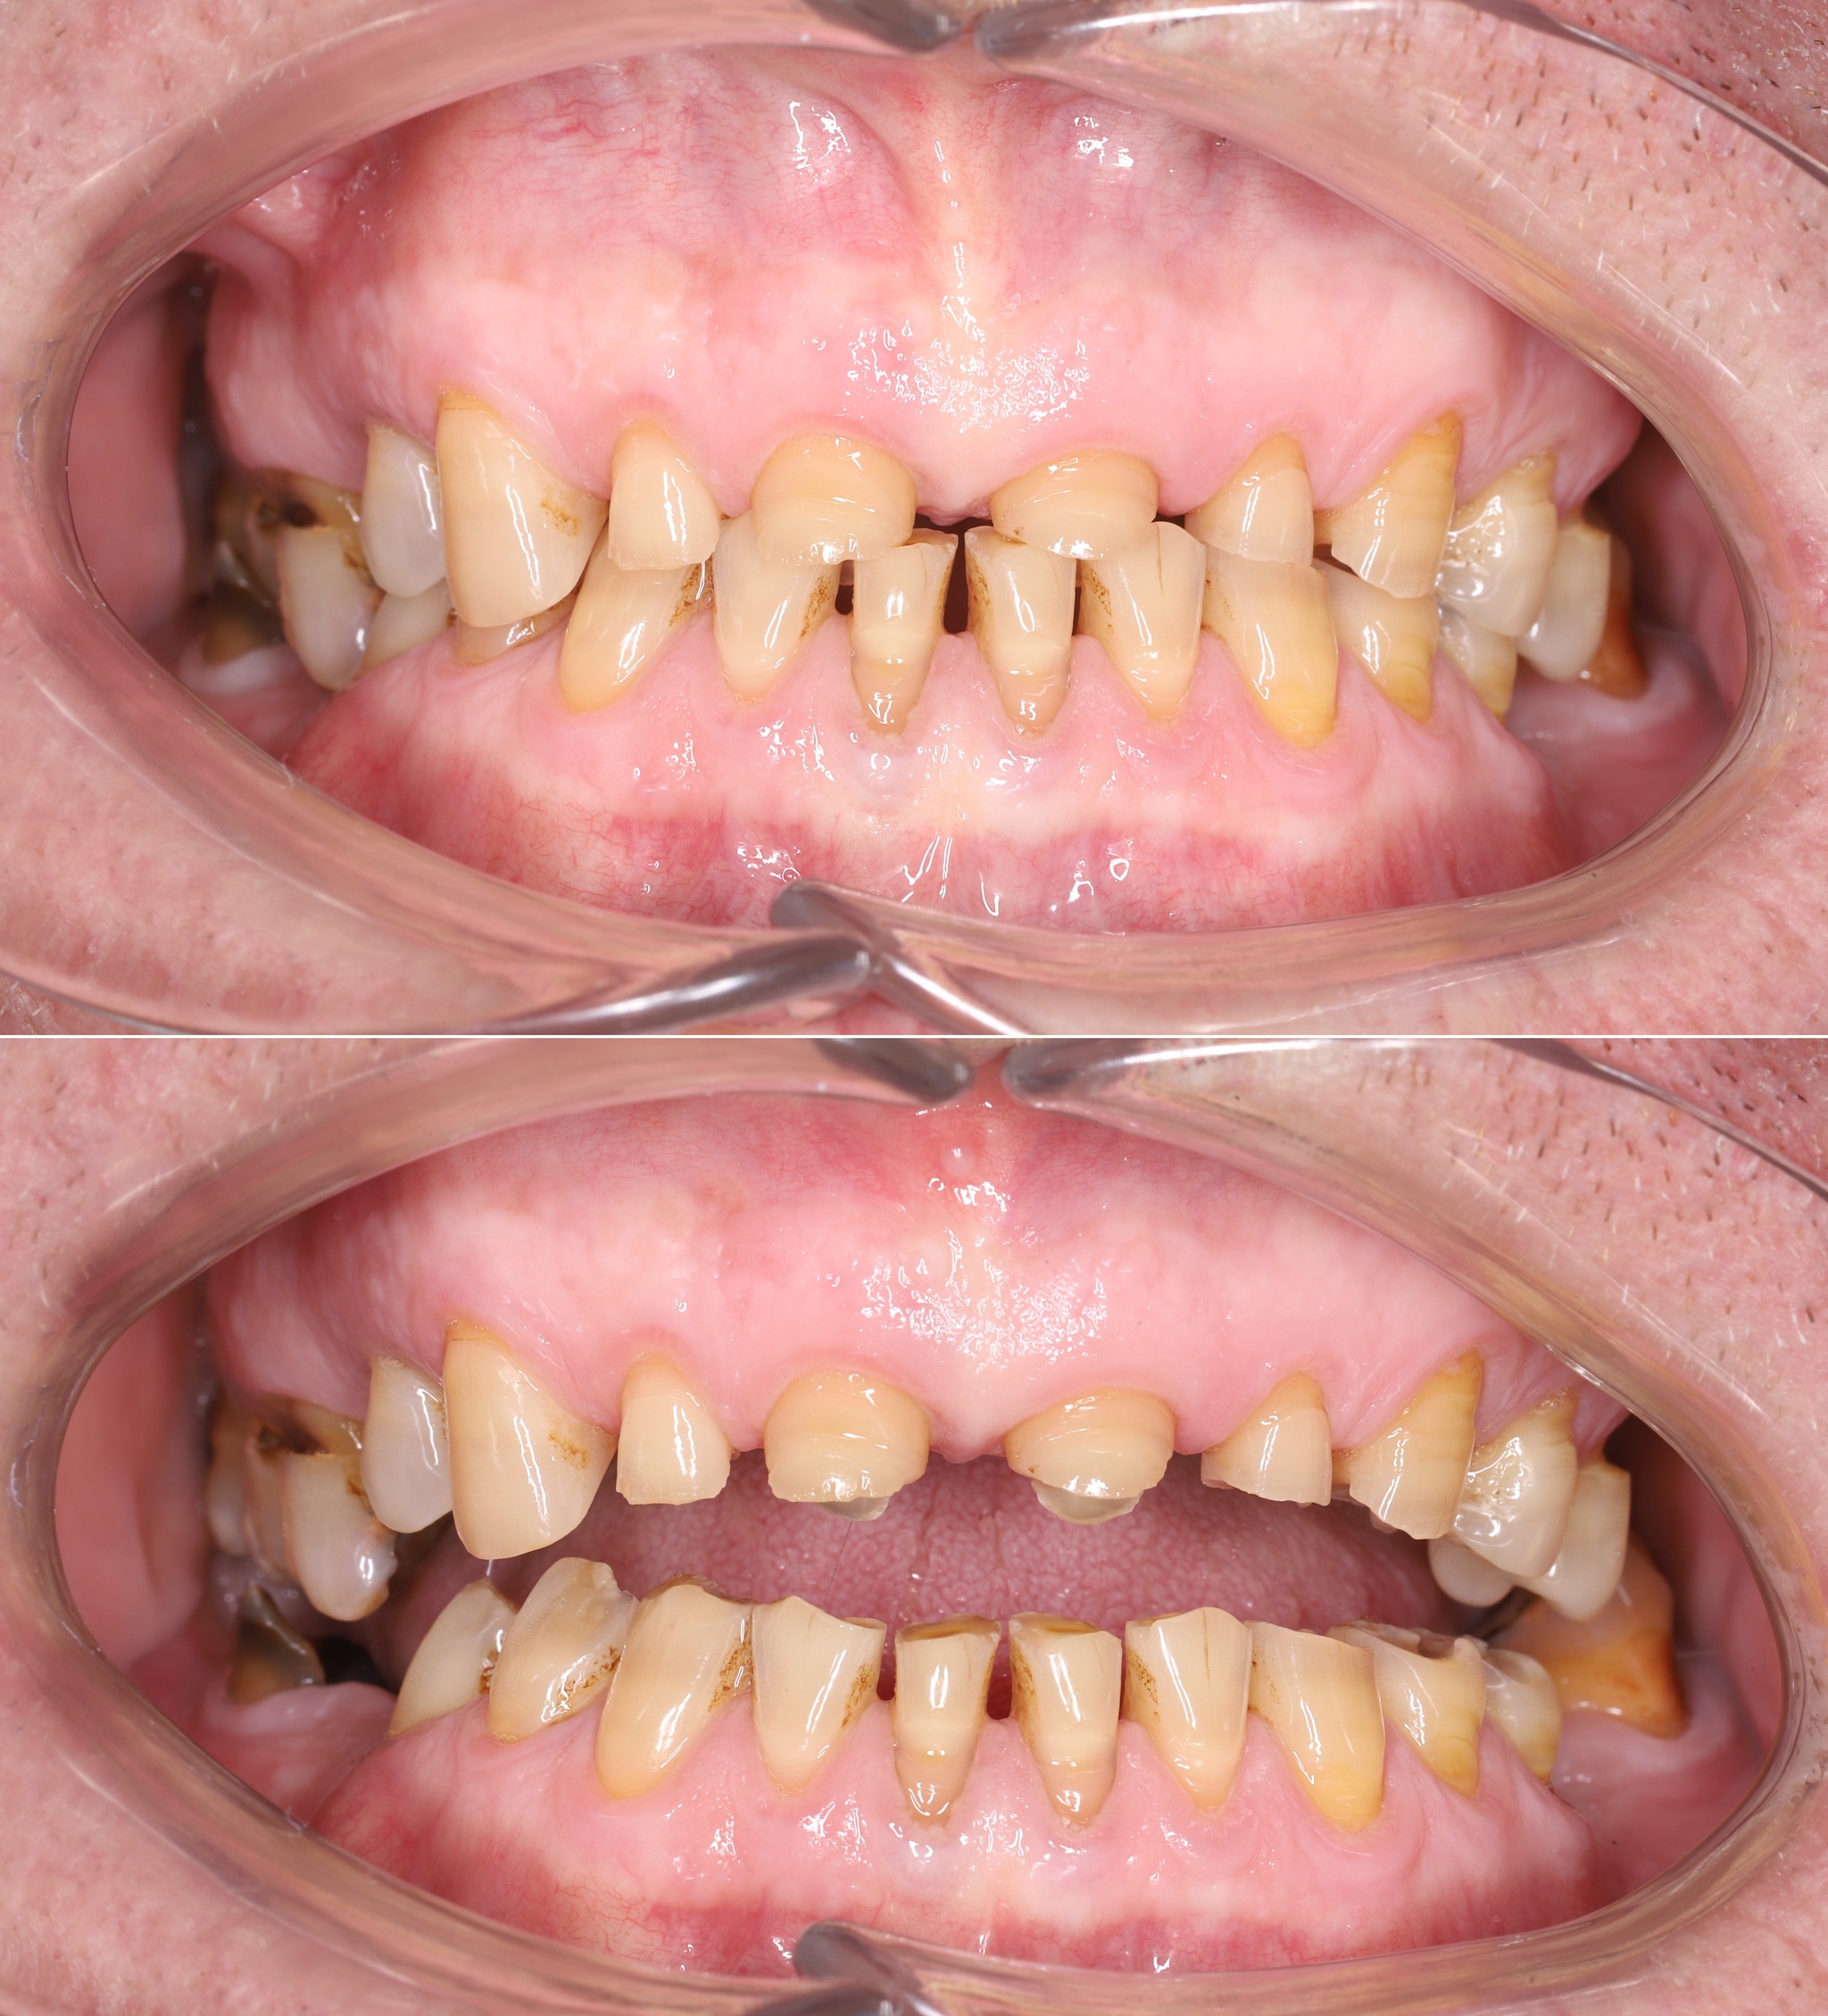

В полости рта ситуация выглядит так:

Отмечается сильная истираемость зубов в связи с длительным отсутсвием полноценного контакта в жевательном отделе.

В связи с тем, что Руслан приезжает из другого города, первым делом я провел удаление всех зубов, которые невозможно было сохранить. Потому как часики тикают, а заживление после удаления занимает около 2 - 3 месяцев.